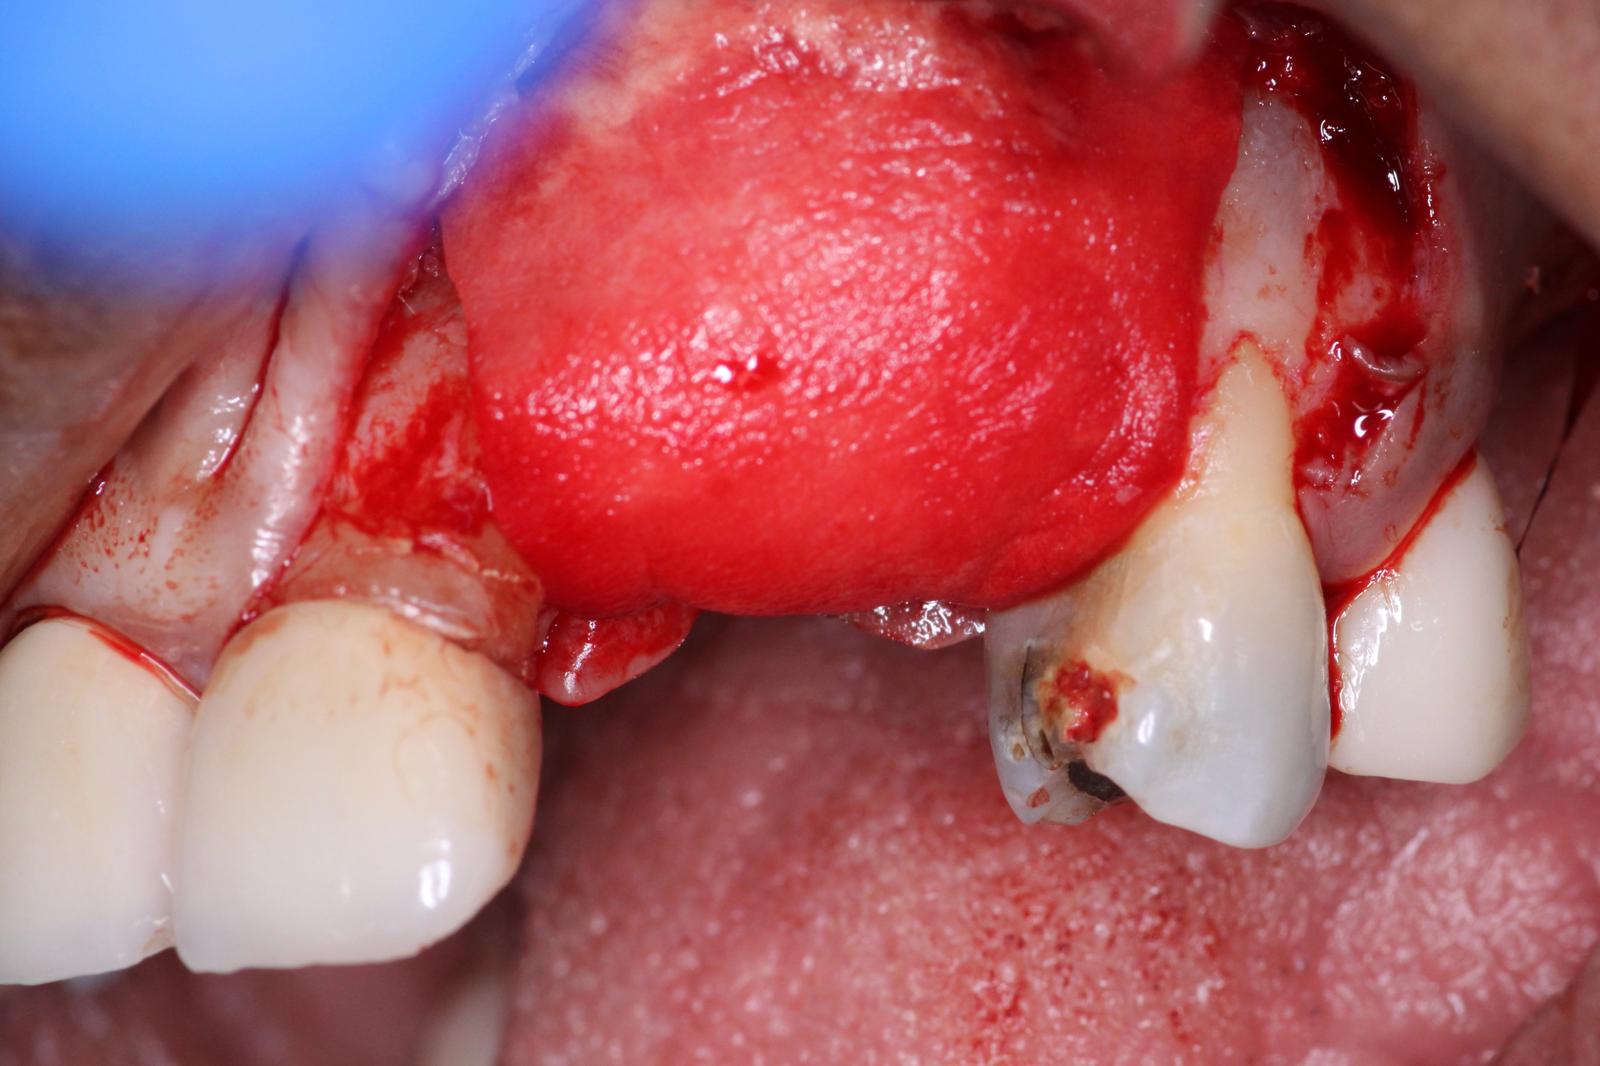

A Full thickness flap was reflected to expose the defect. You can see how severe the defect is, in both the vertical and horizontal dimensions. This is going to be a challenging GBR procedure, and we wanted to use the best materials at our disposal to encourage bone growth.